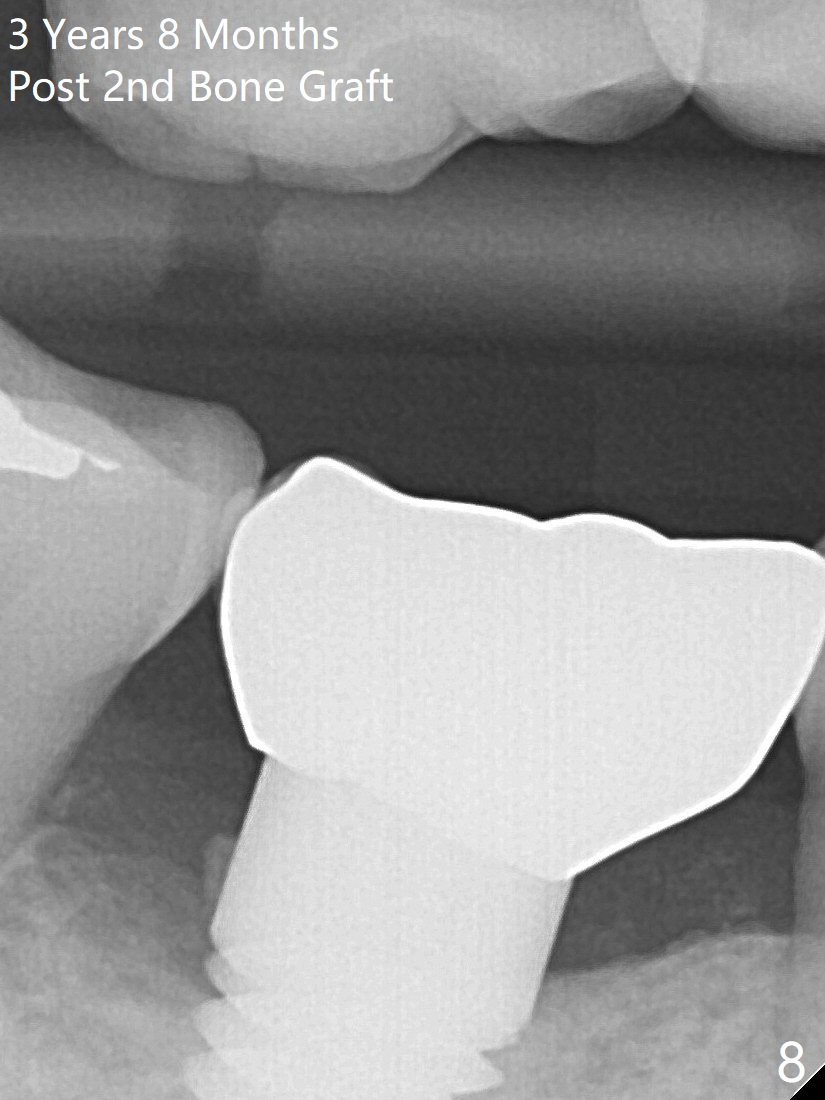

2nd Bone Graft

Thirteen months post bone graft via buccal approach, the patient has remained asymptomatic. There is no sign of infection buccally (Fig.1), but the lingual gingiva is erythematous (Fig.2 arrowheads) with deep pocket (Fig.3). Since the patient will be out of country for 7 months, exploration is going to be done immediately. Preop PA reveals mesial bone loss (Fig.4 M).

There is no symptom or sign of periimplantitis 3 years 8 months post 2nd bone graft (Fig.7-10). However, the patient complains of gingival hemorrhage 8 months later (Fig.11,12 (buccal), 13 (lingual view)). Water Pik is recommended.